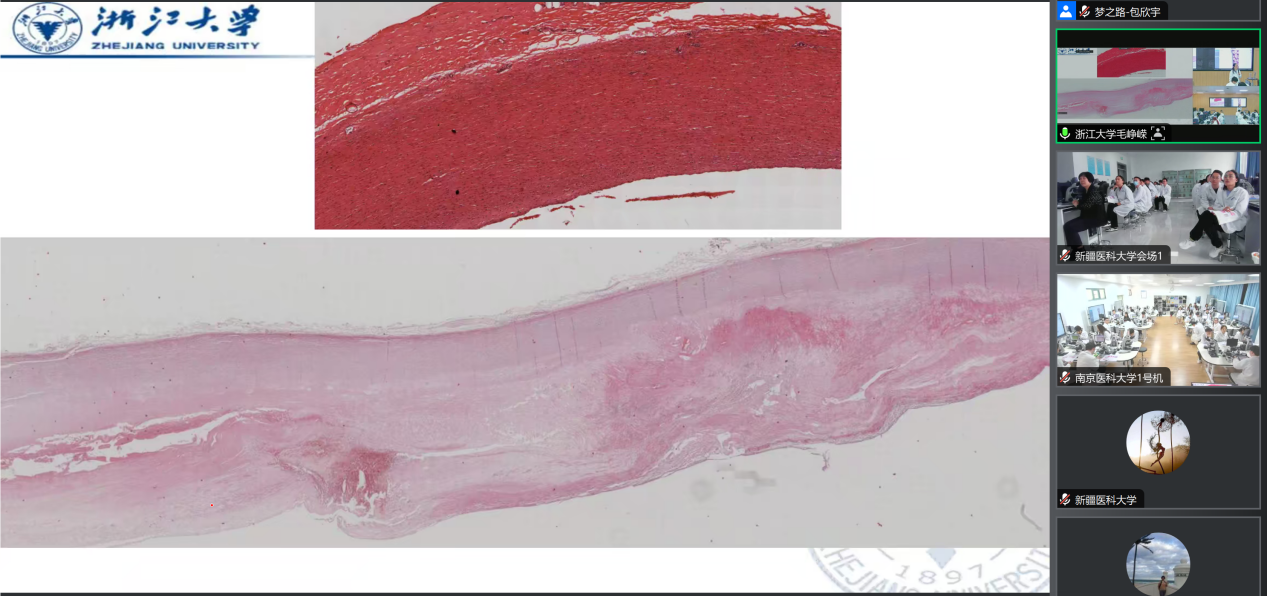

镜下切片观察讲解